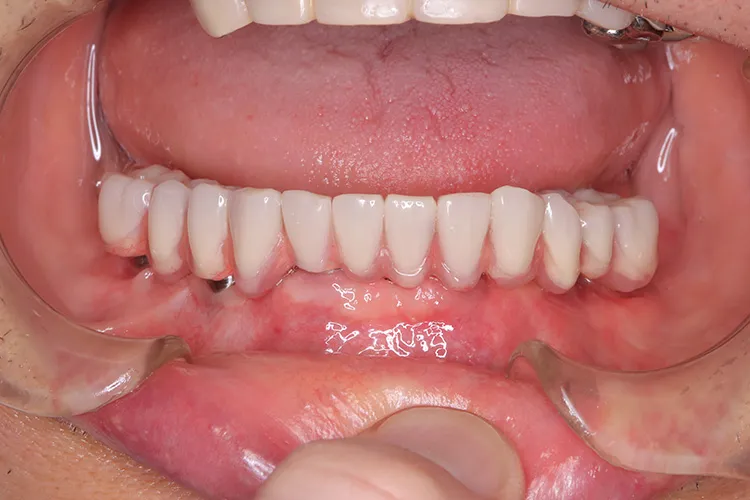

症例8/

下顎ボーンアンカードブリッジ

- 治療期間

- 6ヶ月

- 費用

- 265万円(税込)

治療前

治療後

レントゲン画像

治療内容

ボーンアンカードブリッジの下顎症例です。同じようにインプラント6本で上部構造を支えることができます。